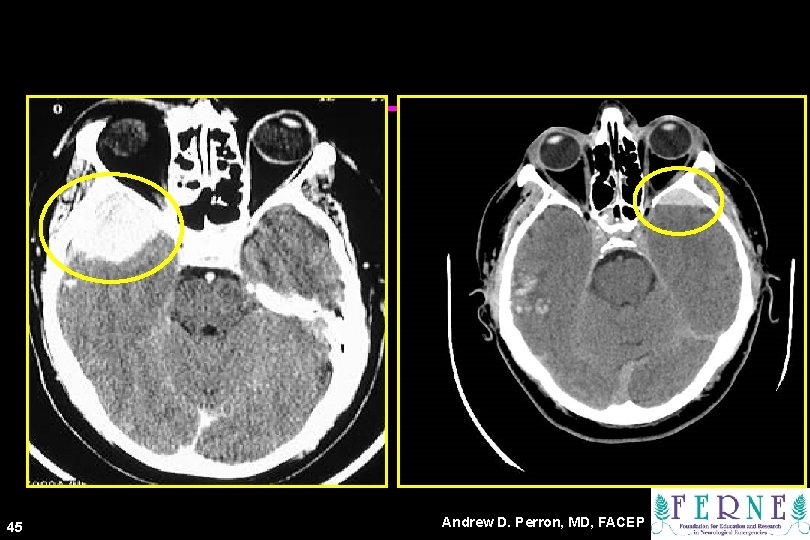

Epidural Hematoma • Lens shaped • Does not cross sutures • Classically described with injury to middle meningeal artery • Low mortality if treated prior to unconsciousness ( < 20%) 43 Andrew D. Perron, MD, FACEP

CT Scans 45 Andrew D. Perron, MD, FACEP

Subdural Hematoma 46 • Typically falx or sickleshaped. • Crosses sutures, but does not cross midline. • Acute subdural is a marker for severe head injury. (Mortality approaches 80%) • Chronic subdural usually slow venous bleed and well tolerated. Andrew D. Perron, MD, FACEP